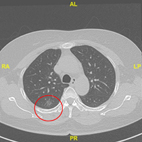

LDCT 健檢發現早期肺癌